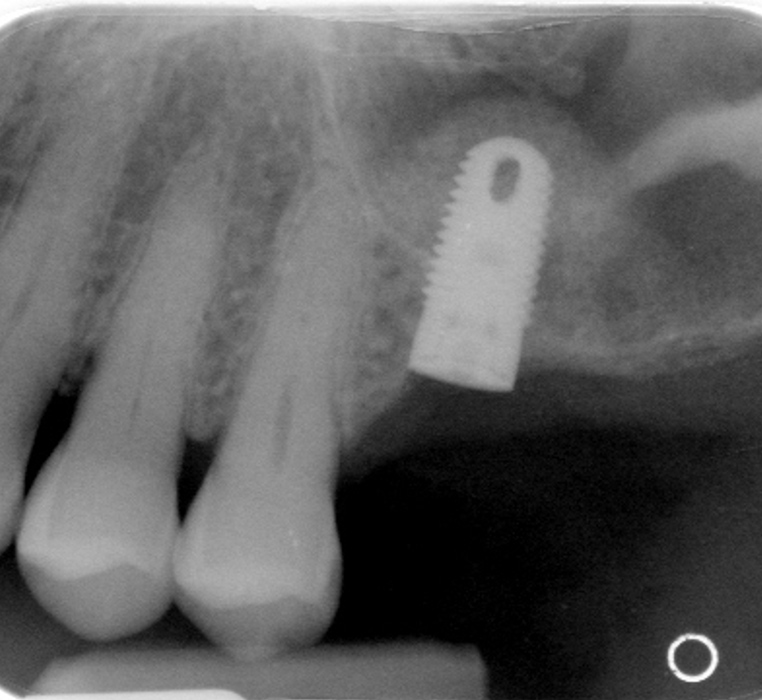

Left Maxillary Sinus Graft for Dental Implant

Before

After